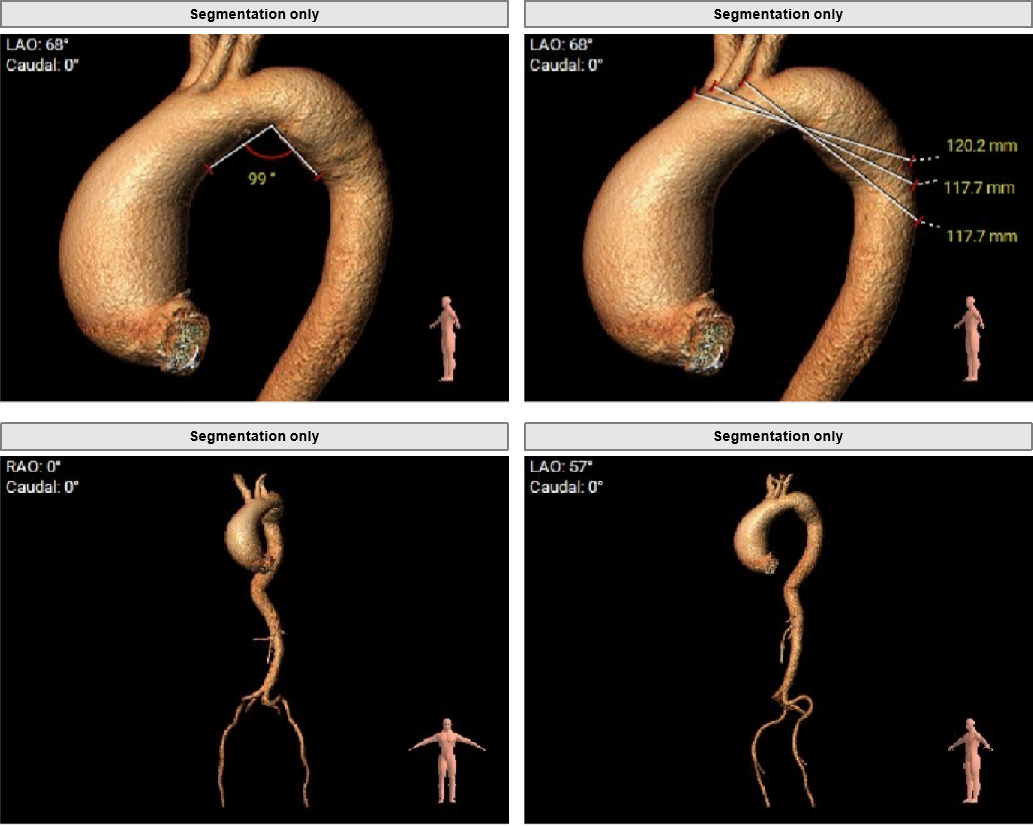

主动脉根部评估

Type1型左右融合二叶式主动脉瓣。

瓣环周长84.7mm,平均周长径27.0mm。

LVOT周长91.7mm,平均周长径 29.2mm。

SOV瓦式窦:36.6mm *35.6mm*39.8mm。

STJ平面周长117.8mm。

升主动脉最大直径66.5mm。

瓣叶重度钙化合并增厚,钙化分布不均,主要集中于左右融合部。

HU419 积分3291mm²。

左冠高度17.9mm,右冠高度13.5mm。

瓣口对应瓣叶稍冗长,术中须注意冠脉风险。

主动脉弓角度与宽度可,心脏水平夹角68°,横位心。

左室腔内径尚可,心室壁稍增厚。